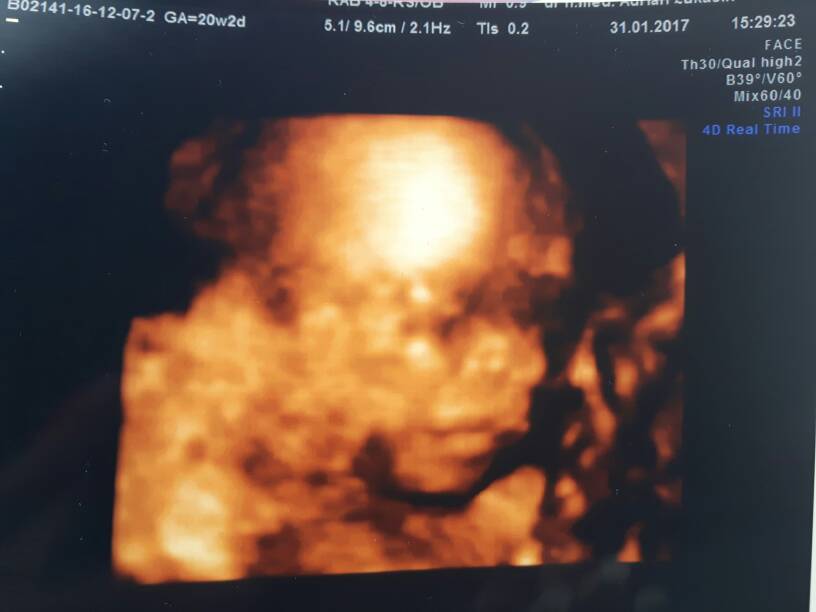

Ja tez nie dotykam . I leżę 80% dnia. [emoji4] cieszę się z każdego dnia dopiero 21 tydzień i mam nadzieję , że dotrwam ładnie do końca. Tryskam optymizmem bo miałam prenatalne we wtorek , teraz wizyta u gina i z maleństwem wszystko super ze mną też nie najgorzej. [emoji4][emoji4][emoji4] a za was trzymam kciuki [emoji4]

20170131_151611.jpg

Ale słodziak chłopiec czy dziewczynka? takie wiadomości uskrzydlają :) oby ich więcej u każdej z nas :)